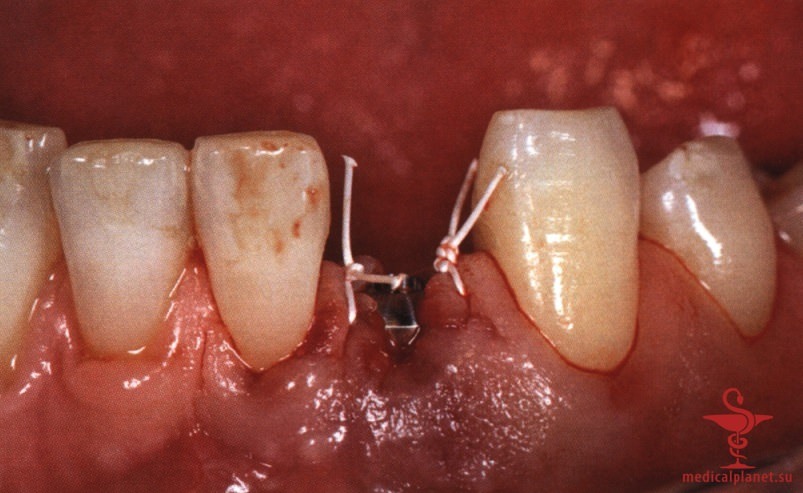

В качестве альтернативы можно провести пересадку субэпителиального соединительнотканного трансплантата (СТТ) для перекрывания лунки, избегая коронального смещения лоскута. Однако следует помнить, что выполнение нескольких хирургических манипуляций одновременно повышает риск нарушения кровоснабжения, от которого во многом зависит качество заживления. При этом часть СТТ остается открытой и заживает вторичным натяжением в течение относительно длительного периода.

Более того, происходит потеря объема трансплантата, а результат редко можно признать оптимальным, особенно в области десневых сосочков (рис. 2), поэтому в настоящее время такой протокол не рекомендуется.